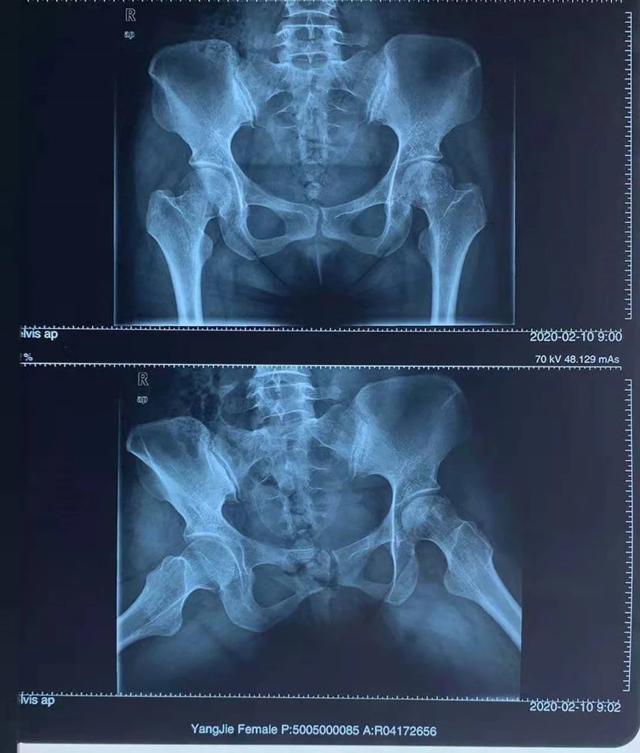

到了III期时,表现为更强烈的且持续性地髋关节疼痛,且站立时髋关节疼痛严重。微观上,股骨头囊状改变明显,硬化性死骨面积较大,股骨头软骨完全断裂,股骨头表面软骨粗糙,股骨头塌陷、扁平,髋关节间隙狭窄或消失。